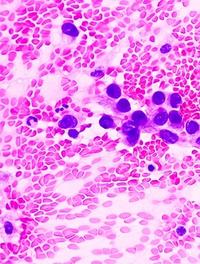

Les méningiomes sont les tumeurs primitives intracrâniennes les plus fréquentes chez l’adulte (40 % des cas). Ils se développent à partir de l’arachnoïde, un des feuillets des leptoméninges, situées à la face interne de la dure-mère. Le risque de développer un méningiome augmente avec l’âge et est deux fois plus élevé chez la femme que chez l’homme. Le traitement repose principalement sur l’exérèse chirurgicale.